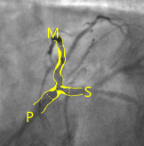

- Specific analysis services: Angiography (coronary and peripheral),Intravascular imaging (OCT- IVUS), QFR, iFR, MRI, Echocardiography (TTE, TEE), CT-scan (aortic & mitral valves, peripheric), Cardiac MRI, ECG and, aortography.

- Quantitative and qualitative assessments (Angiography, QCA, IVUS, OCT, QFR, ECHO, CT scan, MRI, ECG)

Echocardiography (TTE)